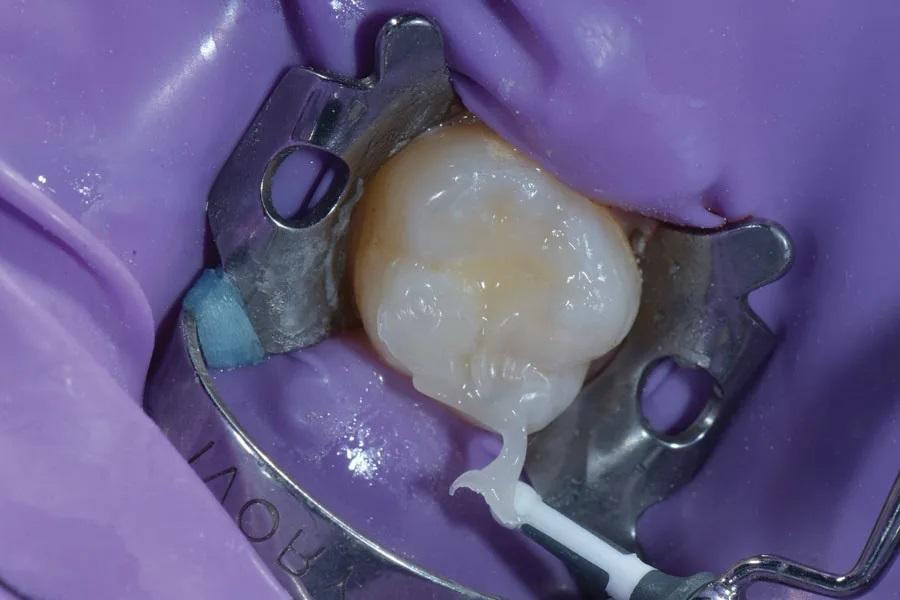

После анестезии зуб 2.6 изолирован коффердамом и частично рассверленным клампом (Фото 2). На всю поверхность непредпрепарированного зуба 2.6 нанесен тонкий слой разделительного агента — вазелина — микрокистью (Micro Applicator, Ultradent). Для изготовления окклюзионного индекса на поверхность зуба нанесен текучий композит для объемного внесения (Admira Fusion x-base, VOCO) (Фото 3). Микрокистью с легким давлением зафиксированы окклюзионные особенности и топография, создав необходимые детали на «штампе». Композит засвечен 20 секунд (Bluephase, Ivoclar); стержень микрокисти внедрен в композит, но не касается анатомии зуба.

Фото 3. После нанесения разделительного средства на непрепарированный зуб 2.6 на поверхность зуба наносили текучий композит и подвергали светоотверждению.

Следует отметить: внедрение стержня микрокисти в окклюзионный «штамп» помогает затем правильно ориентировать его на финальном слое композита при перенесении дооперационной окклюзионной анатомии. Для ориентации также можно пометить отвержденный «штамп» черной точкой по щечному или язычному краю. После отверждения «штамп» снимают с зуба (Фото 4).